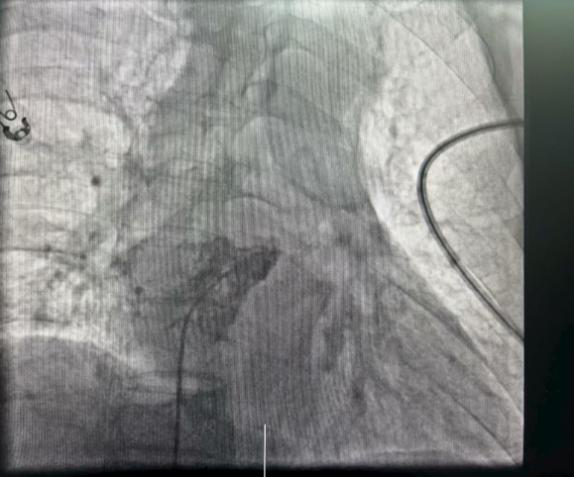

手术团队通过患者股静脉这一微创路径,将仅有传统起搏器十分之一大小的新型无导线起搏器精准输送至右心耳,利用其特有的用于心房起搏的双螺旋设计,起搏器被牢固地锚定在右心耳基底部。整个手术过程顺利,耗时22分钟,术中及术后参数测试均显示起搏器工作状态良好。

成功植入后图片